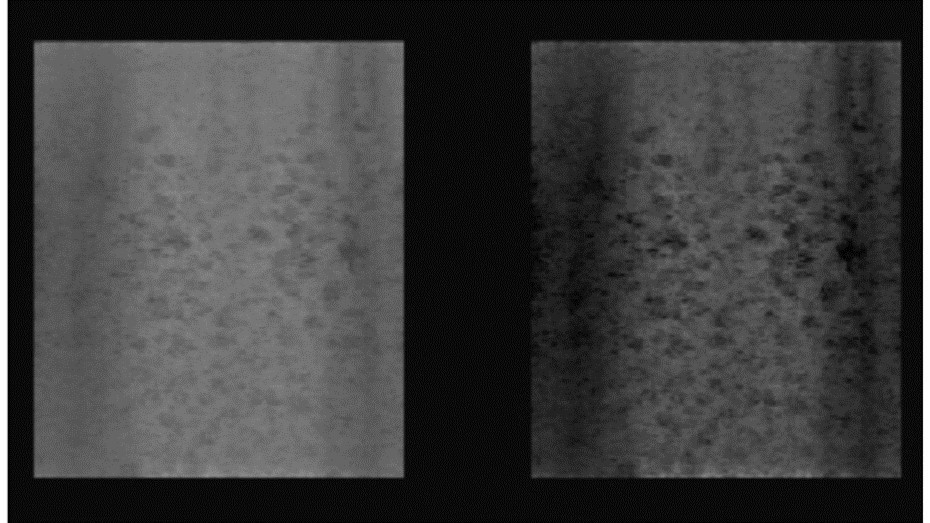

Probes with high acoustic contrast (32.63 dB to 36.66 dB) generated high quality images, Figure 3. Those with acoustic contrast values from 20 dB to 25 dB produced images of lower quality, Figure 4. A typical image produced by a damaged transducer measured as having an acoustic contrast of only 14.68 dB is shown below, Figure 5.

Figure 5.Random Void Phantom) - damaged transducer with inadequate contrast resolution (14.68 dB, Alloca SSD P52105). Original 3D rendered image (left), with increased image contrast (right). Small voids within the RVP with weak contrast cannot be visualised.